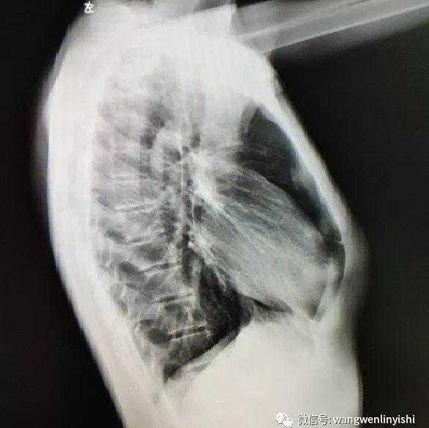

Preoperative Examination

The anterior chest wall was significantly protruded, with a slight depression on the lower half of the chest wall.